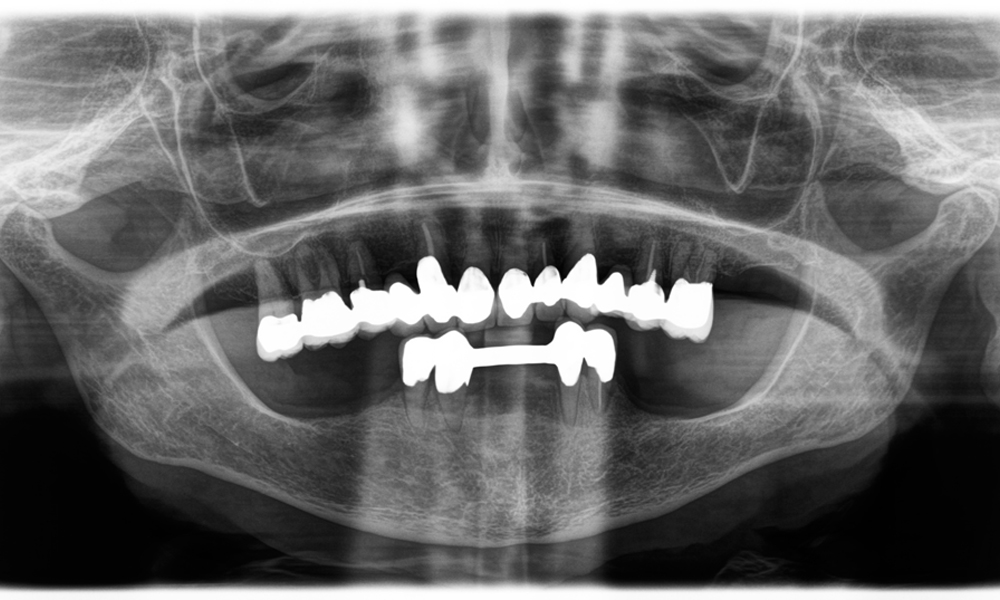

Otro ejemplo del rendimiento clínico de Power Edition fue la sustitución de una corona de zirconio dañada en una paciente de 63 años. El daño se produjo debido a la rotura de una parte del revestimiento de la corona de zirconio de 20 años de antigüedad en el diente 6. A pesar de encontrarse en la zona posterior, a la paciente le molestaba y deseaba una nueva corona.

La Power Edition permitió un corte preciso, en el que el aumento del torque y la mejora de la refrigeración contribuyeron a extraer la corona sin una pérdida significativa de material.

El

sistema de sujeción y el torque mejorado resultaron ser esenciales en este sentido.

Una radiografía que muestra los dientes y una corona de zirconio, sobre un fondo negro.

Figura 2: Sustitución de una corona de zirconio dañada: renovación precisa de una corona de zirconio dañada en el diente 6 con una pérdida mínima de material.